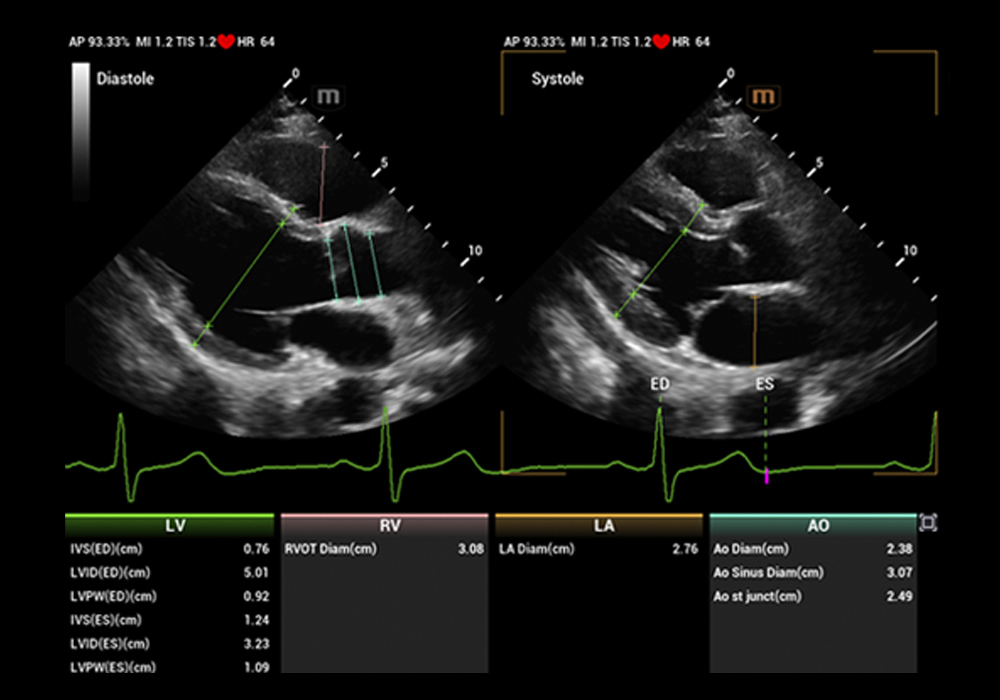

全栈 AI 评估,助力心脏超声步入“全智能”时代,重塑诊疗「体验」

支持多腔室应变评估,全自动化识别、追踪、描迹、分析心脏超声切面,显著提高结果准确性和可重复性

将传统手动心脏参数测量的时间由数十秒缩减至 3s 内,效率提升数十倍

多个检测区,超百项目结构功能参数自动测量 多种频谱类型,百余项血流参数自动测量